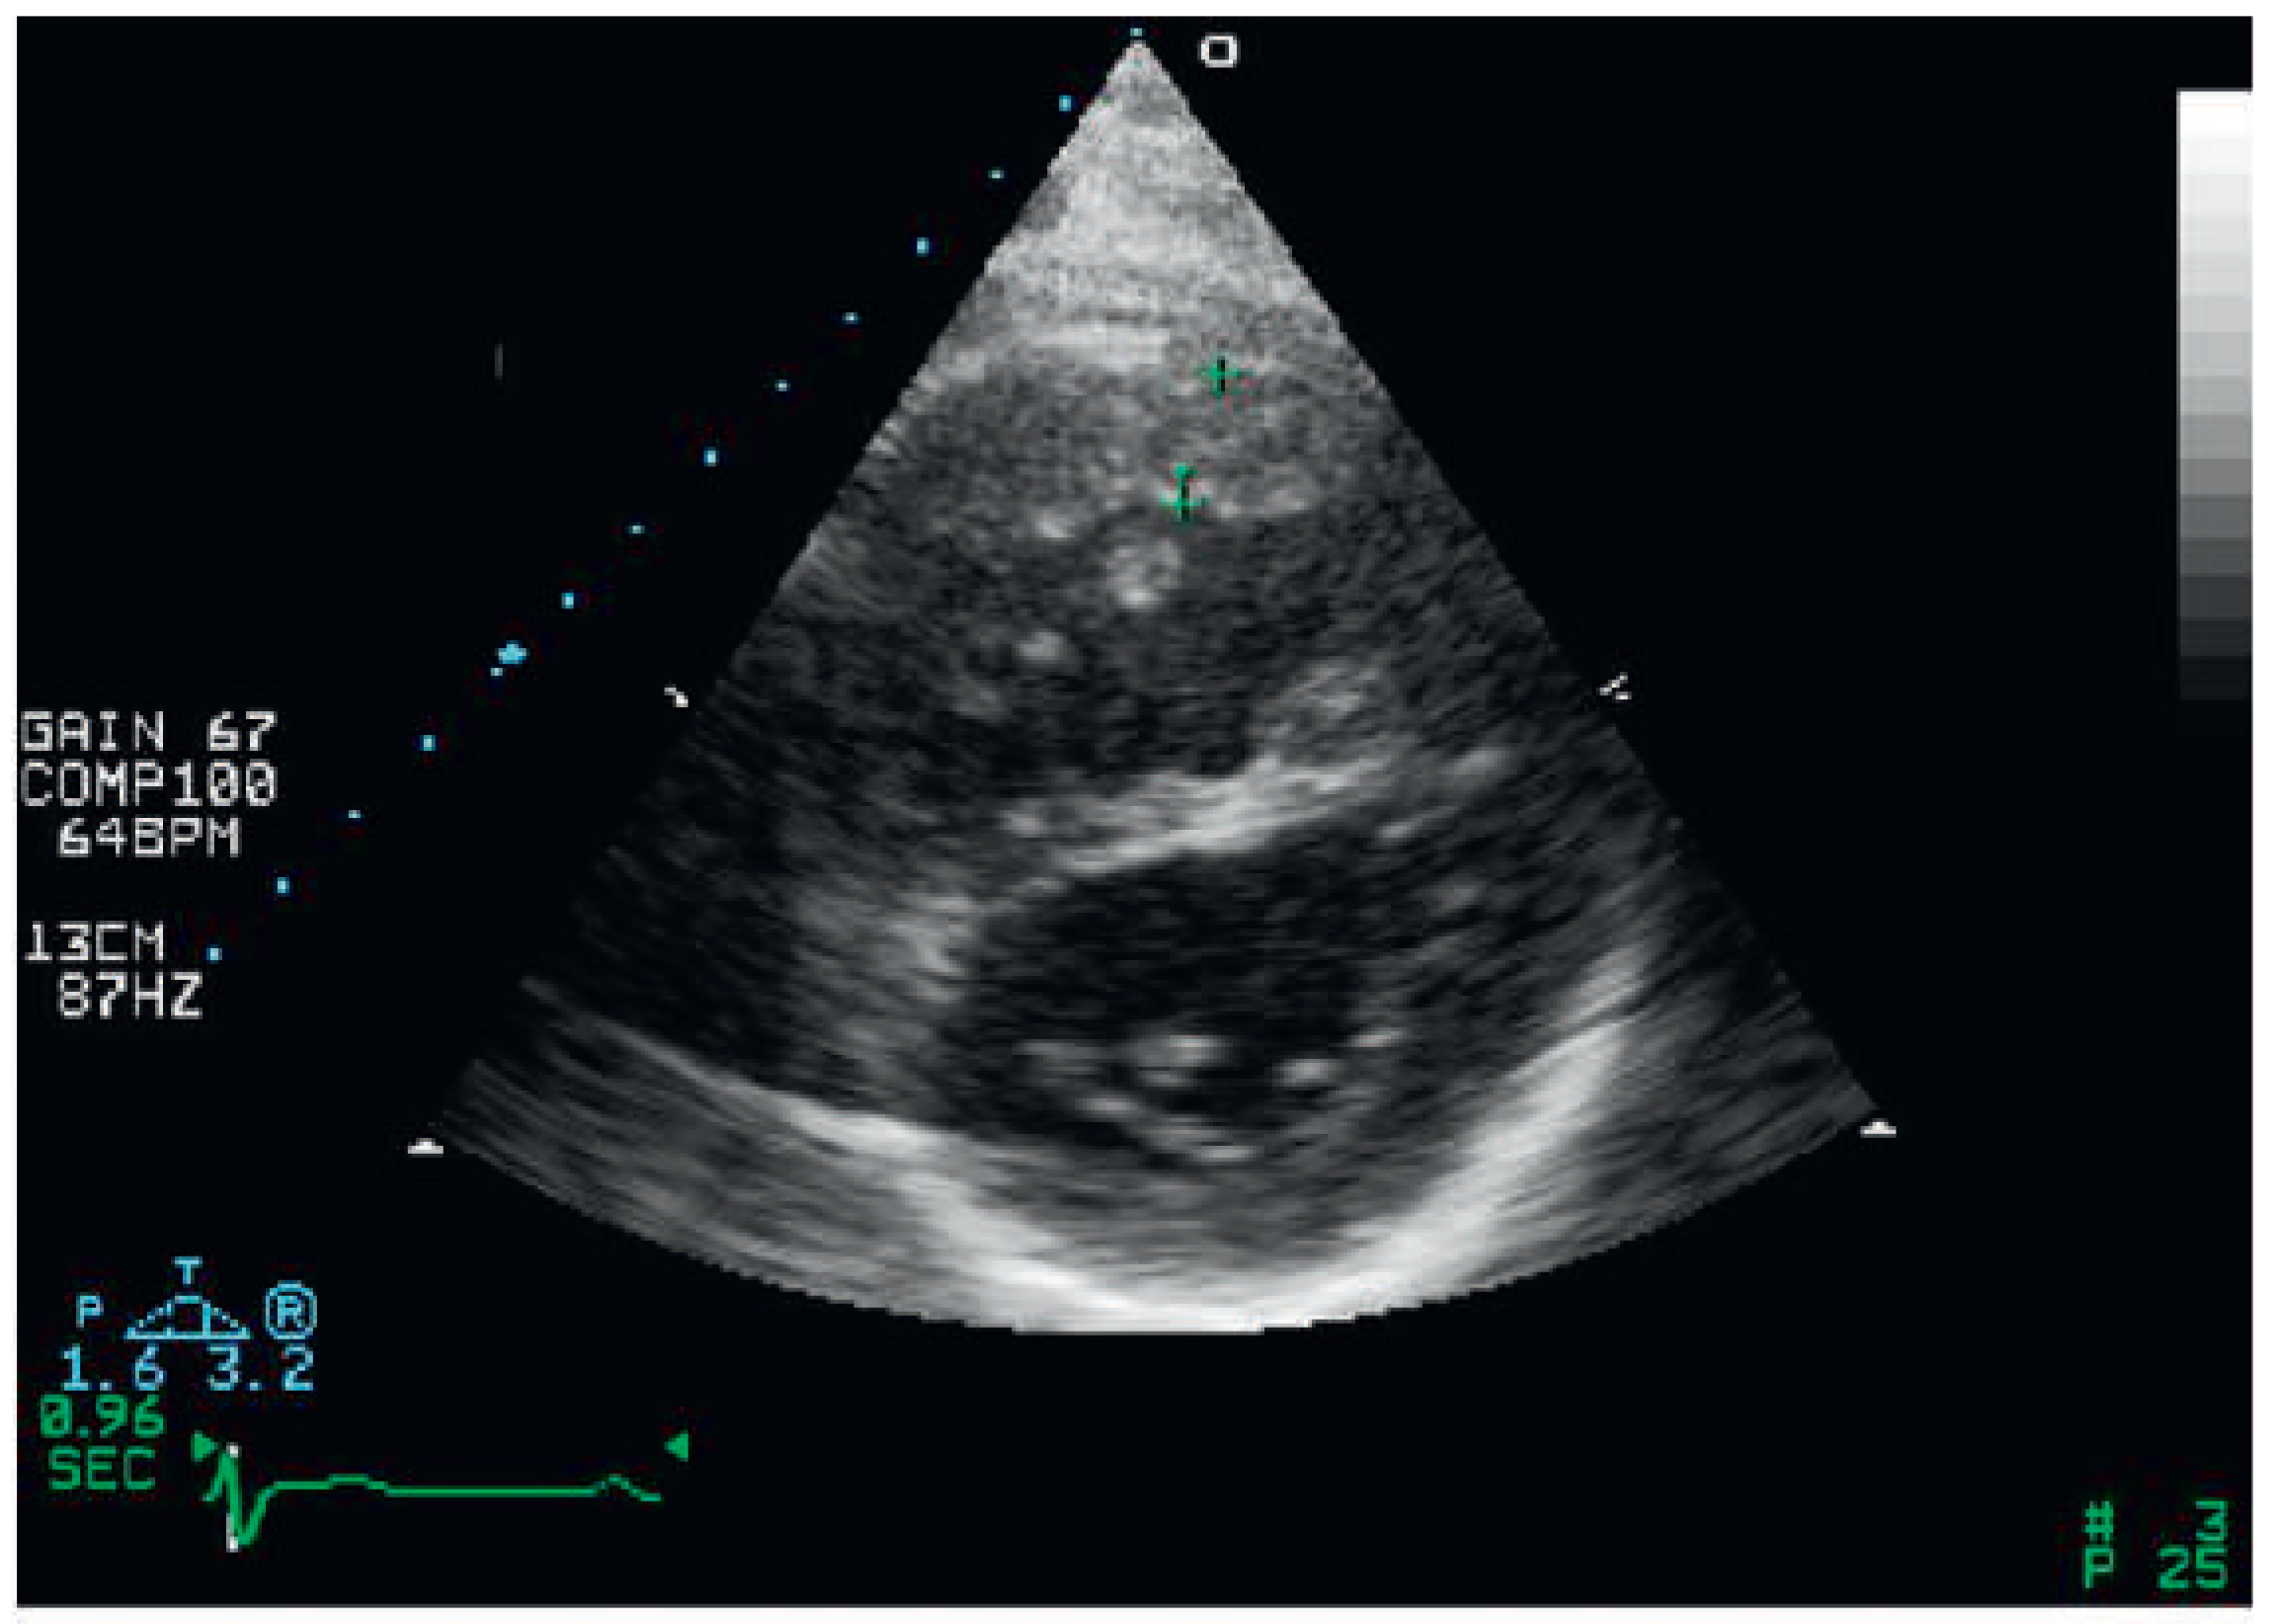

Conventional two-dimensional assessment of the right heart structure

Assessment of the right ventricular function in two-dimensional echocardiography (fractional area change)